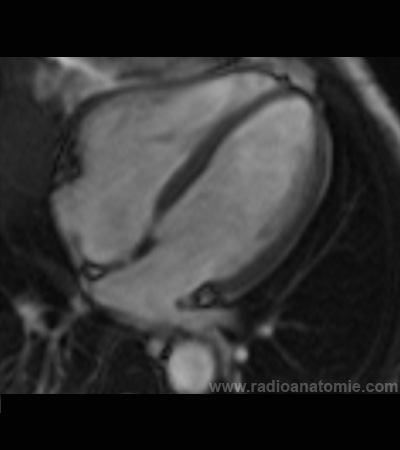

Radioanatomie et plans de coupe en IRM cardiaque

Coupe long axe 4 cavités